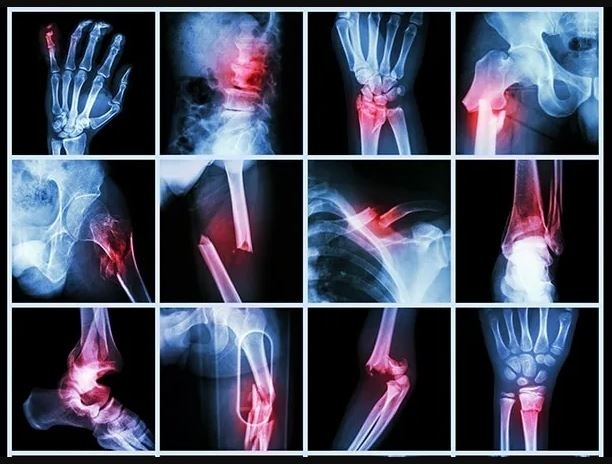

🚨 Боитесь боли после травмы или операции? Это нормально. Но избегание движений — опасно! Друзья, сегодня поговорим о том, что мешает многим начать реабилитацию после травм, операций или переломов — страх боли. Люди часто спрашивают: "А если будет больно? Может, лучше подождать?" Отвечаю, ожидание и избегание движений — это прямой путь к хроническим проблемам. 🤔 Почему нельзя откладывать реабилитацию? Уже через 2–3 недели без движения мышцы теряют до 20% силы (исследование Journal of Applied Physiology). После переломов или операций это означает, что суставы остаются без поддержки, а восстановление затягивается. После операций или травм в тканях образуются рубцы и спайки, которые ограничивают подвижность. Без правильных упражнений сустав может "закостенеть" — и тогда даже простые движения будут вызывать боль. Движение стимулирует лимфодренаж и кровоток. Без него восстановительные процессы замедляются, а отёки и воспаления сохраняются дольше. Парадокс: чем дольше вы избегаете движений,

Друзья, сегодня поговорим о том, что мешает многим начать реабилитацию после травм, операций или переломов — страх боли.

Люди часто спрашивают: "А если будет больно? Может, лучше подождать?" Отвечаю, ожидание и избегание движений — это прямой путь к хроническим проблемам.